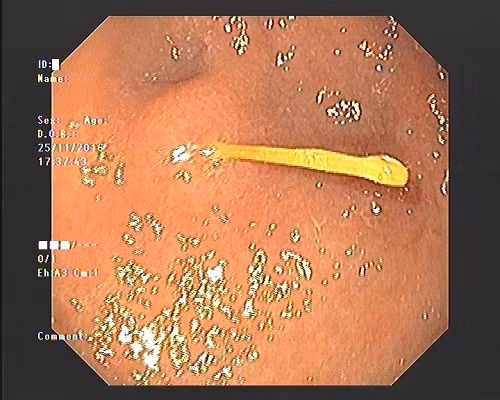

Suýt thủng dạ dày vì vừa ngậm tăm vừa uống nước. Đó là trường hợp của một phụ nữ 45 tuổi ở Nam Từ Liêm, Hà Nội phải vào Bệnh viện E Hà Nội cấp cứu vì đau bụng và đau vùng thượng vị dữ dội. Kết quả thăm khám nội soi tại bệnh viện cho thấy bệnh nhân này bị một vận nhọn đâm và mắc tại hang vị dạ dày. Cây tăm đã làm xung huyết hang vị và gây loét 1cm.

| Hình ảnh tăm đâm thẳng vào dạ dày được phát hiện qua nội soi. Nguồn: Khám Phá. |

Ngoài ra, kết quả nội soi cho thấy từ thực quản xuống đến dạ dày của bệnh nhân này xuất hiện nhiều vết trầy xước... đó chính là gây ra tình trạng đau đớn quằn quại cho bệnh nhân. Được biết trước khi nhập viện 3 ngày nữ bệnh nhân này sau khi ăn cơm tối xong nữ bệnh nhân này vừa xỉa răng vừa uống nước không may nuốt luôn phải cây tăm tre vào bụng.